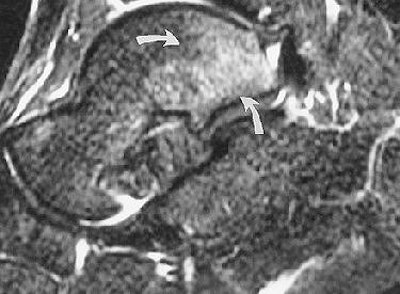

According to the soccer player's results, MR depicted bone marrow edema of the os trigonum, lateral talar tubercle, and subtalar synovitis. No other osseous anomalies and no tibiotalar synovitis or flexor hallicus longus (FHL) tenosynovitis were seen. The PAI diagnosis was established on the basis of MR findings, the group stressed. The patient underwent successful conservative treatment.

| PAI syndrome in a 20-year-old male soccer player. Above, lateral radiograph of the right ankle demonstrates a well-defined os trigonum (arrow). Middle, sagittal T1-weighted image (366/14) shows area of low signal intensity (arrow) within the os trigonum. Below, sagittal, fast spin-echo inversion-recovery image (4,000/69; inversion time, 130 msec) medial to middle image demonstrates bone marrow high signal intensity (arrows) in the posterior talus, consistent with a bone contusion. |

| Figure 1abc. Bureau NJ, Cardinal E, Holden R, Aubin B, "Posterior ankle impingement syndrome: MR imaging findings in seven patients." Radiology 2000; 215:497-503. |

Also in all patients, MR depicted low signal intensity of the os trigonum and/or lateral talar tubercle on T1-weighted images, as well as high signal intensity on fat-suppressed T2-weighted imaging. These signs were consistent with bone marrow edema. A major advantage that MR has over x-ray or CT is the ability to depict bone contusions or occult fractures as their presence may influence treatment, they added.